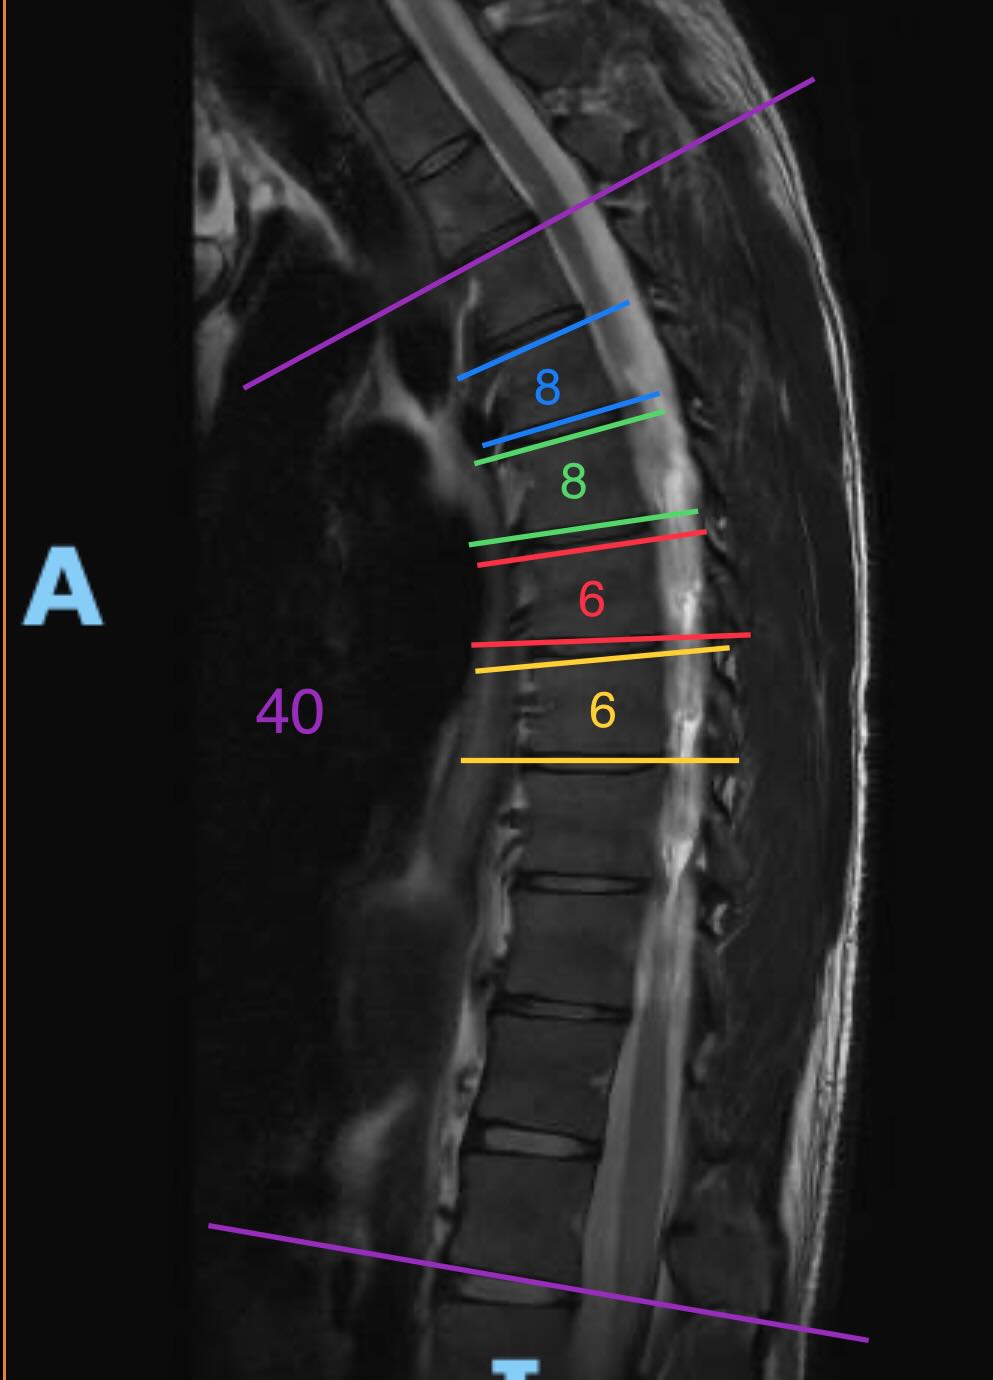

Die Bilder (Winkel von mir eingezeichnet und gemessen):

Ich habe keine Ahnung was mit Irregularitäten gemeint ist. Eine Grad-Zahl der Kyphose wurde auch keine genannt.Es zeigen sich tatsächlich mindestens drei Wirbelkörper leicht keilwirbelförmig konfiguriert (Cobb-Winkel >5 Grad), dies ist ein diagnostisches Kriterium des Morbus Scheuermann. Allerdings fehlen die für den Morbus Scheuermann typischen anterior betonten Irregularitäten respektive sind nur sehr diskret ausgebildet. Somit kann weder eindeutig die Diagnose eines Morbus Scheuermann gestellt werden noch kann dieser ausgeschlossen werden.

- Ist das anhand des Bildes eine leichte/mittlere/stärkere Hyperkyphose?

- Ist der Cobb-Winkel überhaupt klar definiert/normiert? Aus meiner Sicht macht es absolut keinen Sinn, eine Seitenaufnahme der Wirbelsäule zu machen, und dann den Winkel zwischen zwei bestimmten Wirbelkörper zu messen. Das Ergebnis ist offensichtlich massiv beeinflussbar von der Haltung, die man einnimmt. Bei einem MRI liegt man sogar. Und im Stehen kann ich beliebig steuern, wie stark der Rücken krümmt, von "Arme ganz nach vorne hängen lassen" bis maximale Aufrichtung unter massiver Anstrengung. Für mich ein Mysterium, warum alle immer von diesem Winkel reden, wenn er doch sehr wenig aussagt. Würde man jetzt den Grad der Verkeilung von gewissen Wirbelkörpern messen und addieren, hätte man schon ein viel objektiveres Ergebnis.